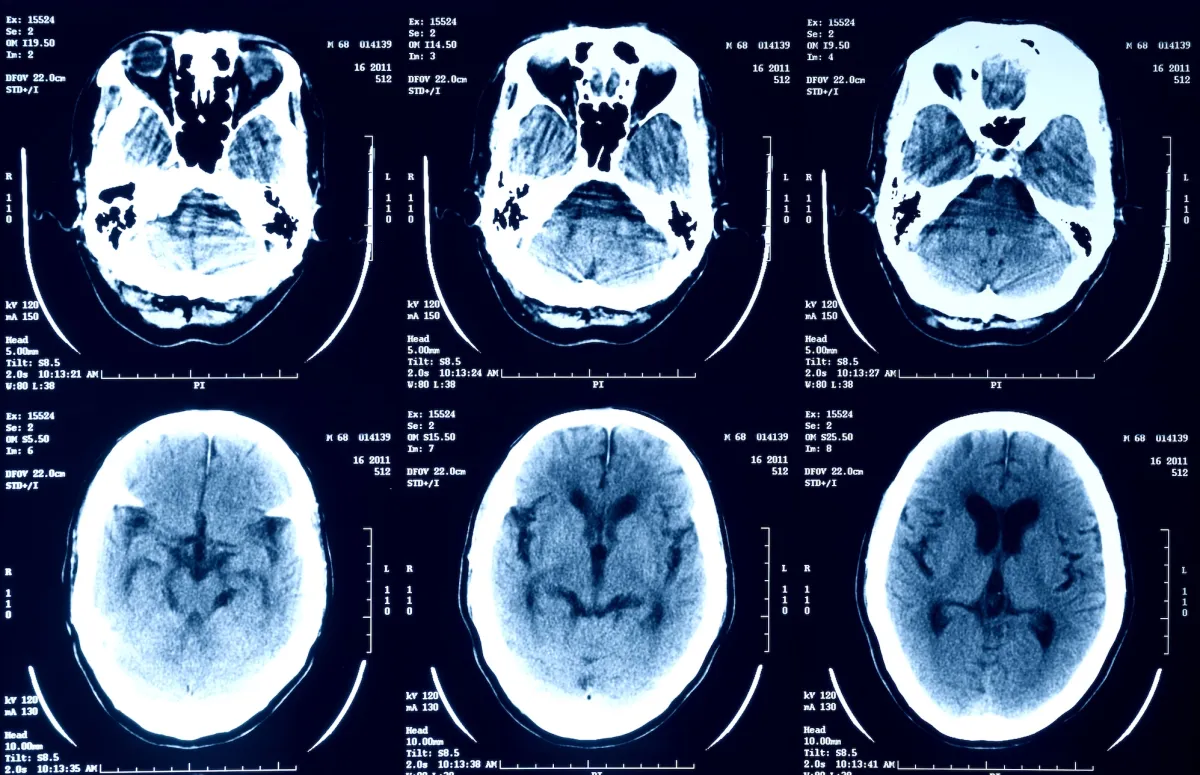

Một số ứng dụng thậm chí đã phát triển AI để đưa ra phán đoán về các triệu chứng cụ thể, chẳng hạn kiểm tra tình trạng sức khỏe của vùng kín. Gần đây, từ tháng 10, nền tảng mạng xã hội X (trước đây là Twitter) đã khuyến khích người dùng tải lên hình ảnh X-quang, MRI và PET để chatbot AI Grok phân tích và diễn giải. Việc này đặt ra nhiều mối quan ngại nghiêm trọng về quyền riêng tư và bảo mật dữ liệu y tế. Dữ liệu y tế thuộc loại nhạy cảm và được bảo vệ nghiêm ngặt bởi luật pháp liên bang Mỹ. Tuy nhiên, người dùng có thể dễ dàng đánh mất quyền kiểm soát khi tự ý tải lên những thông tin nhạy cảm này. Các chuyên gia an ninh mạng cảnh báo rằng bất kỳ dữ liệu nào được tải lên đều có thể trở thành “nguyên liệu” để kẻ xấu lợi dụng, tiềm ẩn nguy cơ lộ thông tin nhạy cảm.

Trên mạng xã hội X, Elon Musk đã khuyến khích người dùng tải lên hình ảnh y tế của họ để AI Grok phân tích. Dù thừa nhận rằng kết quả của Grok vẫn đang ở giai đoạn “sơ khai”, Musk kỳ vọng rằng AI này sẽ cải thiện qua thời gian và trở nên chính xác trong việc giải thích kết quả y tế. Tuy nhiên, chính sách bảo mật của Grok lại không nêu rõ về việc ai có thể truy cập dữ liệu này và liệu dữ liệu sẽ được chia sẻ với những bên nào.